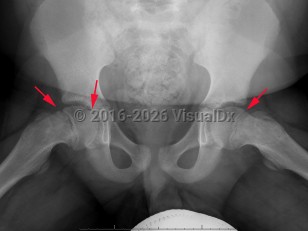

Slipped capital femoral epiphysis

Pathophysiology: SCFE occurs due to mechanical forces acting on the growth plate as there is a weakness in the hypertrophic zone. In adolescents, there are increased shearing forces as the growth plate is still vertical and the perichondrial ring is thin and weakened. These increased shearing forces result in the femoral head shifting off the femoral neck through the growth plate.

Another classification tool is the Southwick slip angle classification. This uses the epiphyseal-diaphyseal angle, which can be measured on both anteroposterior (AP) and frog-leg lateral pelvis imaging. SCFE can be classified as mild if the angle is less than 30 degrees, moderate if between 30 and 50 degrees, and severe if greater than 50 degrees.